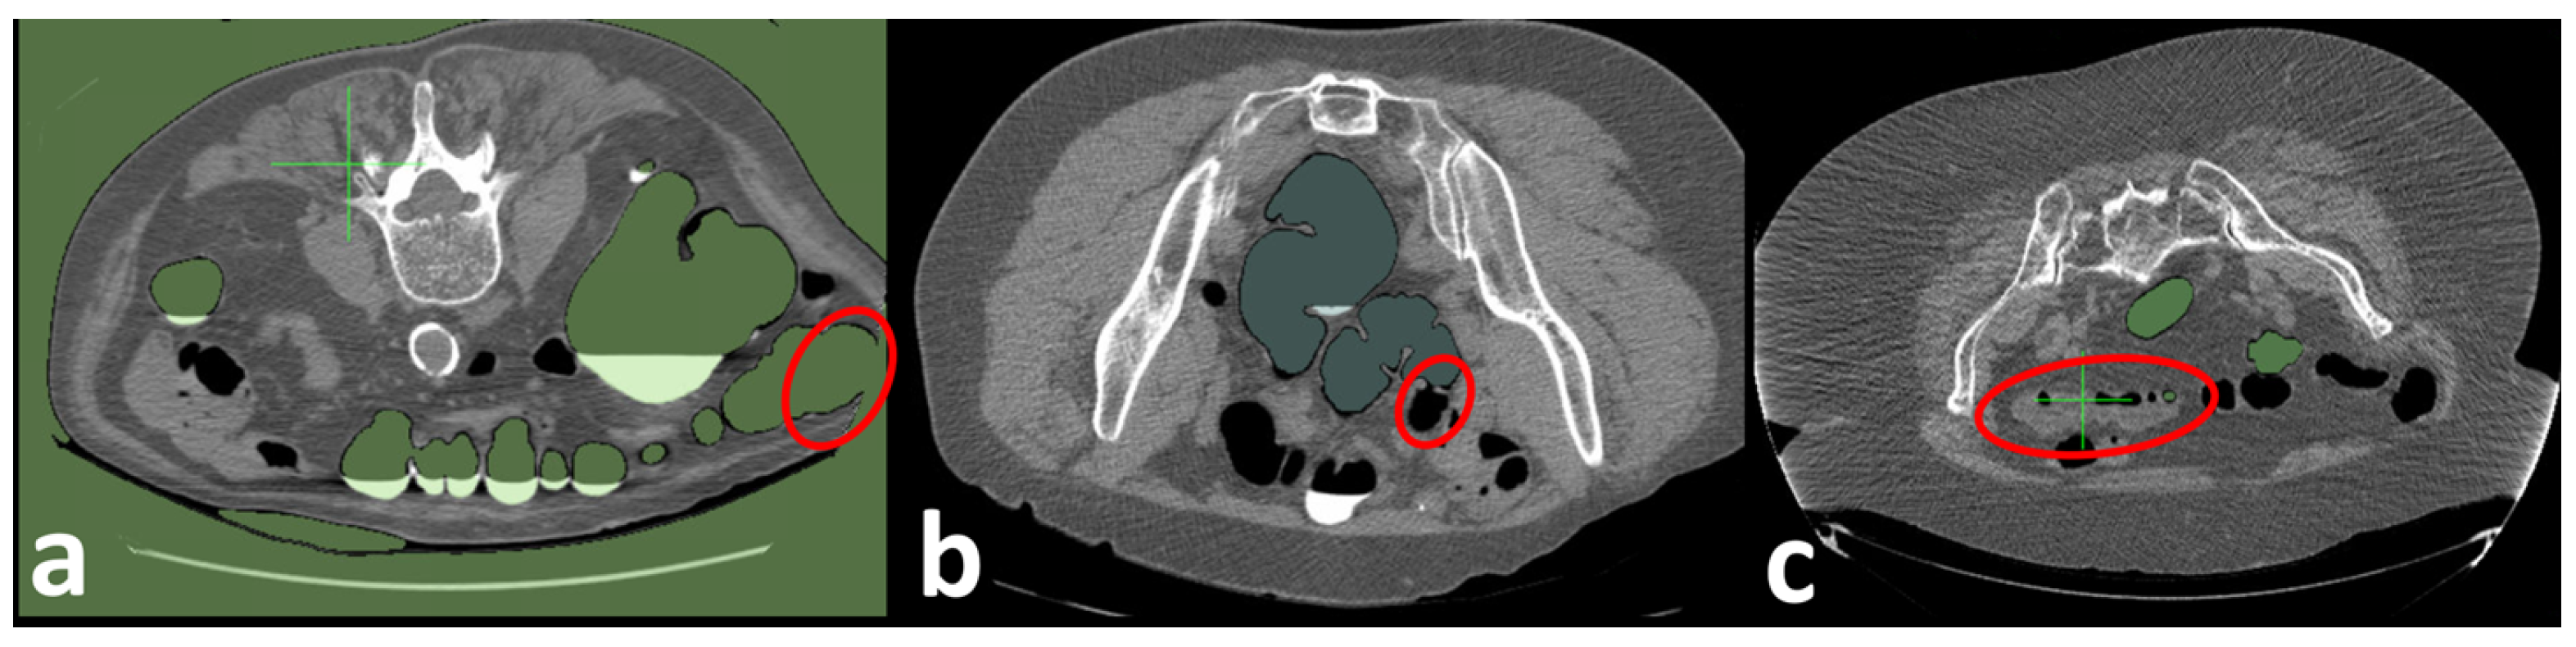

Figure 7.

A patient with a 1.7 cm pedunculated polyp in the sigmoid colon. (a) Standard-dose CT is scanned (120 kVp/240 mAs). (b) Low-Dose CT is simulated using a noise insertion model (60 kVp). (c) Enhanced Low-Dose CT using FBP + U-Net back-projection approach [,].

We simulate the reduction in the tube peak voltages using CT, starting from the standard tube peak voltages of 120 kV, to obtain CTs with different dose levels (80, 60, and 30 KV). A U-Net model is trained on the LoDoPaB-CT Dataset [] to obtain the reconstructed enhanced CT. Figure 7(ii) shows an example of low-dose and enhanced CT images using the proposed algorithm. As shown in Figure 7, the FI visualization of the enhanced low-dose CTC is very close to the original standard-dose CTC visualization, while the FI visualization of the low-dose CT misses the polyp.